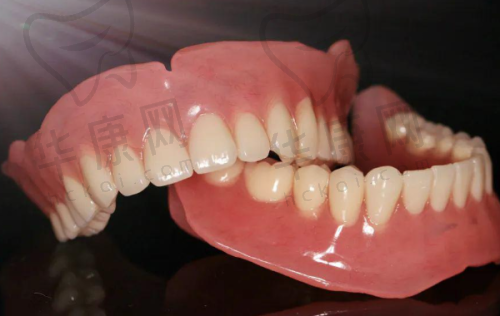

在网络上,也有特别多患者分享了自己在该医院进行树脂贴面治疗的经历。他们上传了治疗前后的对比照片,让更多人直观地看到了树脂贴面的神奇成效。这些真实的实例和好评,进一步提升了医院的口碑和有名度。